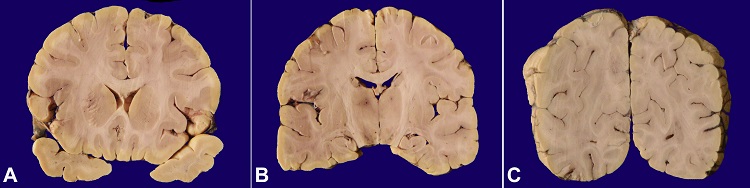

The brain, at autopsy, weighed 1300 g (mean Reference range 1240 g). There were no exudates on the convexities of the brain base. The leptomeninges were translucent. There were mild uncal notching and tonsillar herniation, indicating cerebral edema. Coronal slices revealed focal prominence of the intraparenchymal vessels in all the slices. No focal lesions were identified. The striate cortex showed softening and irregular grey-white junction bilaterally (Figures 22C).

At gross, despite the absence of any mass-like lesions, they produce subtle changes of loss of grey-white distinction, the granularity of the parenchyma, and edema.5 On imaging, primary CNS lymphomas present as homogeneously enhancing periventricular or superficial lesions that are iso to hypodense on CT, iso or hypointense on T1 and hypointense to grey matter on T2.14 Lymphomatosis cerebri, on the other hand, presents as diffuse and asymmetric, abnormal T2-hyperintensity in deep and subcortical white matter with involvement of corpus callosum. Contrast-enhancement pattern may vary from no-enhancement to patchy non-mass-like enhancement or nodular/mass-like enhancement..15 Intravascular lymphoma (IL) is an important differential diagnosis on imaging and may presents with infarct-like lesions, nonspecific diffuse white matter lesions, meningeal enhancement, or large mass-like lesions.16 It needs mention and differentiation from LC; the neoplastic cells in this entity (IL) selectively grow within the lumens of small vessels and capillaries and do not form mass lesions. This pattern is likely caused by a defect in the homing receptors in the neoplastic cells.17 Other differentials include diffuse glioma (gliomatosis cerebri), progressive multifocal leukoencephalopathy (PMLE), vasculitis, microangiopathy, and demyelination.10 The diffuse infiltration of the brain parenchyma evident in gliomatosis Is a potential diagnostic pitfall; however, immunoreactivity for glial fibrillary acidic protein (GFAP) distinguishes the former from the latter. Likewise, the splitting of argyrophilic fibers around the vessels in case of LC and PCNSL, brings vasculitis and microangiopathy amongst the differentials. The neoplastic nature of the infiltrate within the vessels helps in resolving the diagnostic dilemma. Demyelination noted in cases of PMLE typically affects the white matter anywhere within the central nervous system. It is caused due to the JC virus, the inclusions of which are evident in the oligodendrocytes as ground-glass nuclei, and reveals positivity with SV40 immunohistochemistry.18